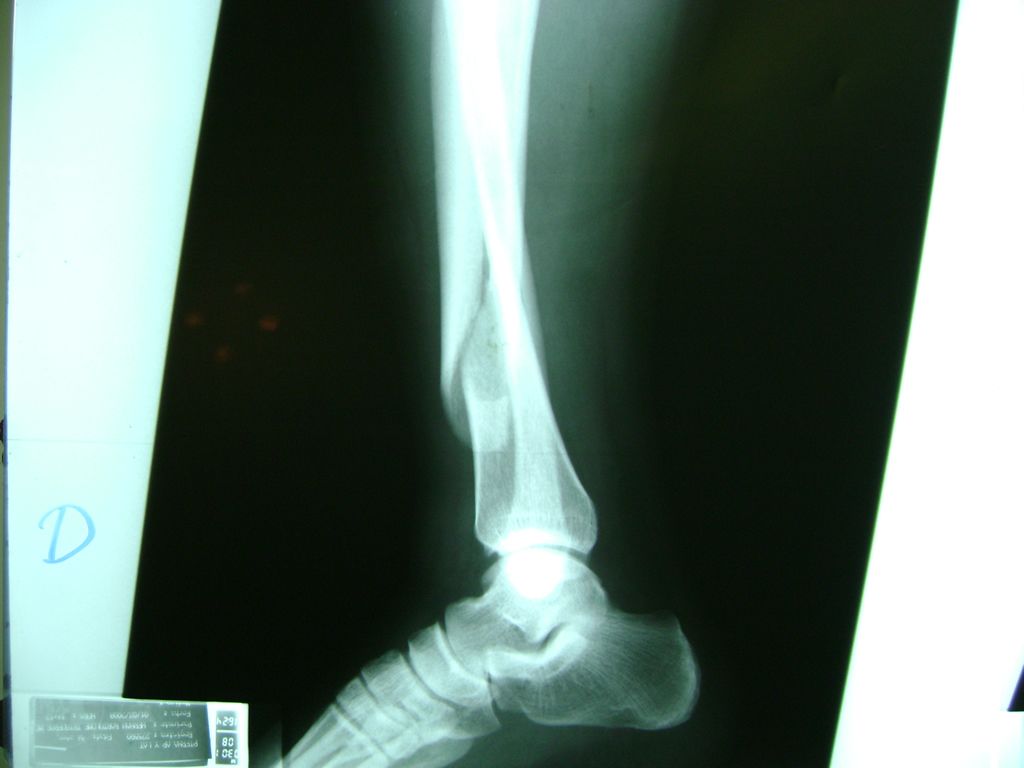

Cirugía de Tibia y Peroné

Aunque cada uno de estos huesos puede fracturarse por separado, normalmente la rotura es una lesión que se produce de forma conjunta

La mayor parte de las roturas implican a la parte proximal del hueso (parte del hueso próximo a la rodilla) o a la parte distal (parte del hueso cerca del tobillo).

Debido a la fina cobertura de piel que recubre la tibia y el peroné, las fracturas generalmente son abiertas, es decir, el hueso roto rasga la piel, atravesándola. Las fracturas de tibia y peroné generalmente se producen por un fuerte impacto o torsión.